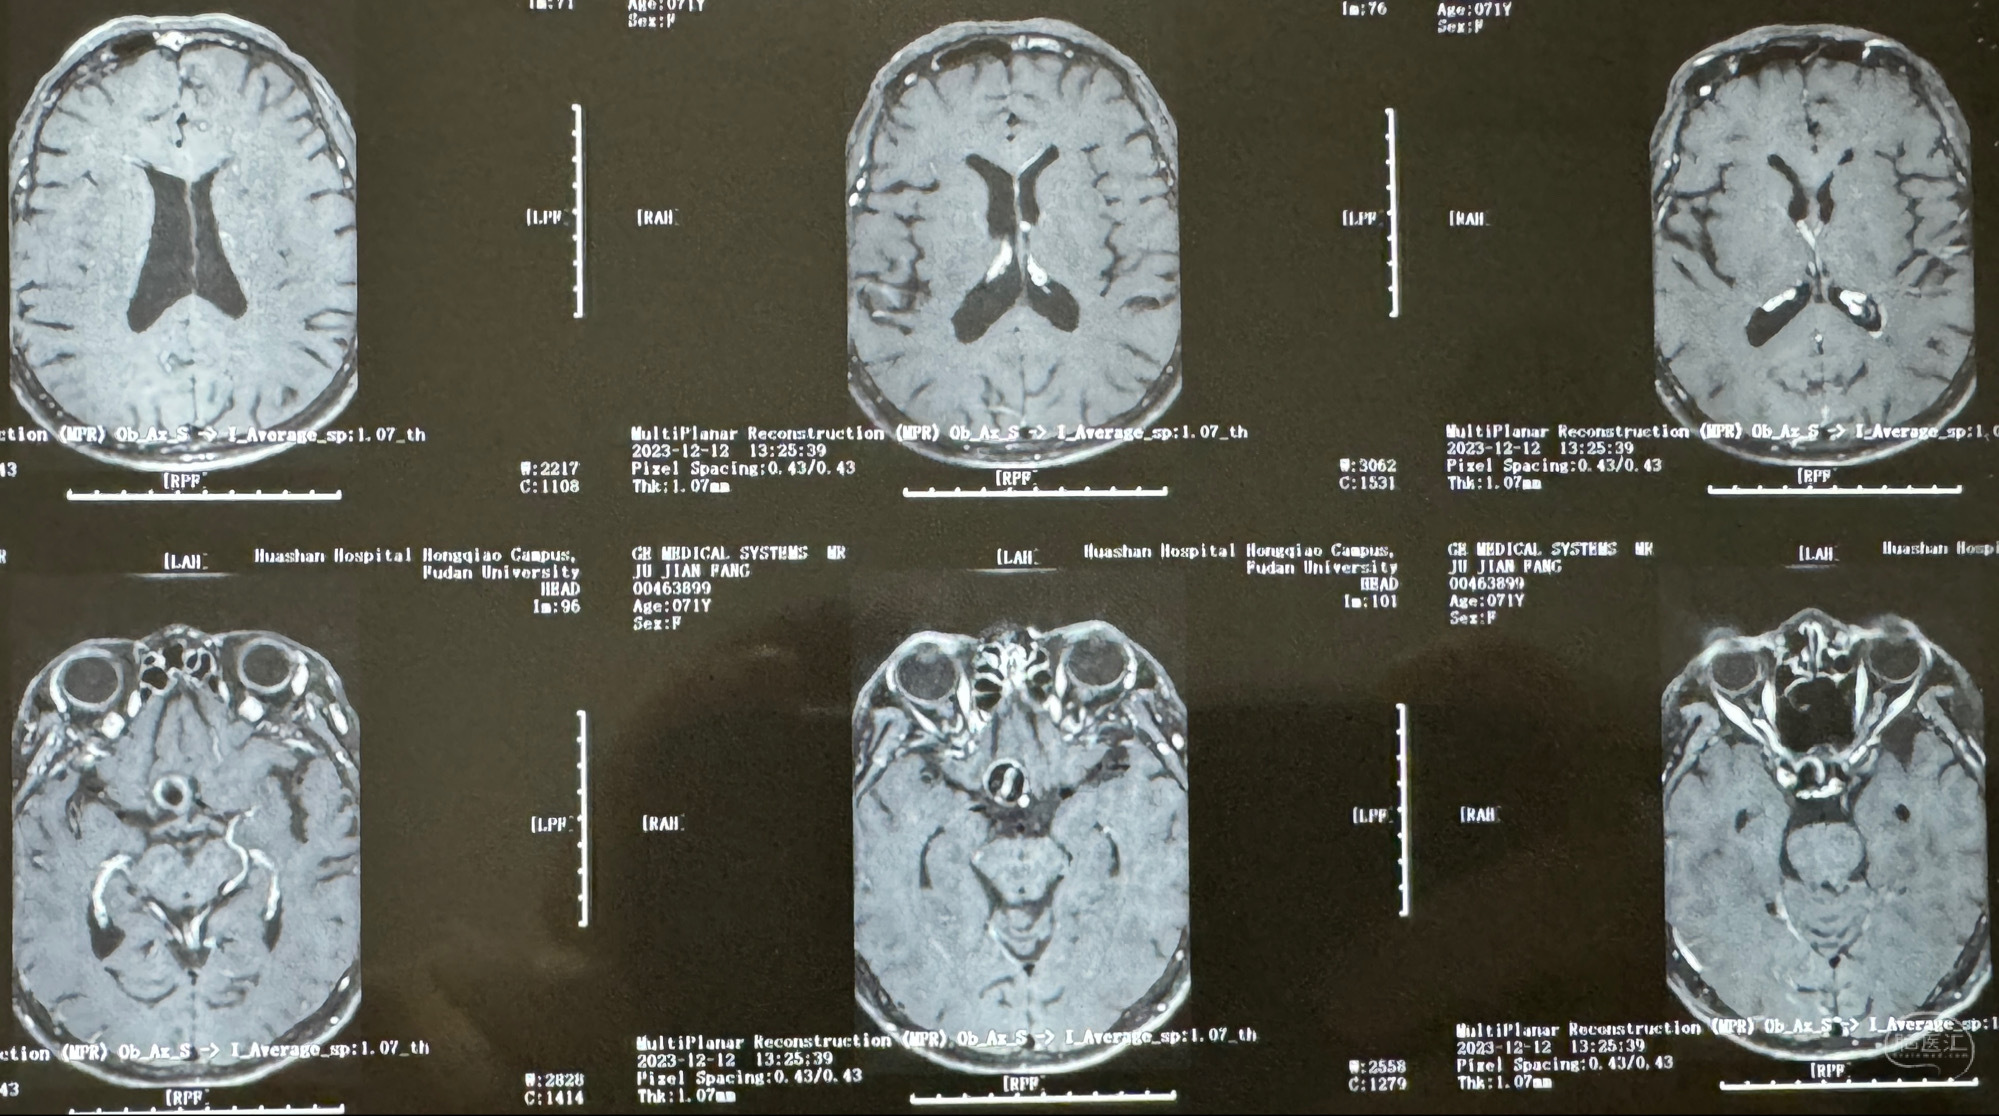

辅助检查;2023-11 外院 头颅MRI+MRA:左侧颈内动脉C6段动脉瘤;

2023-12-12MRI